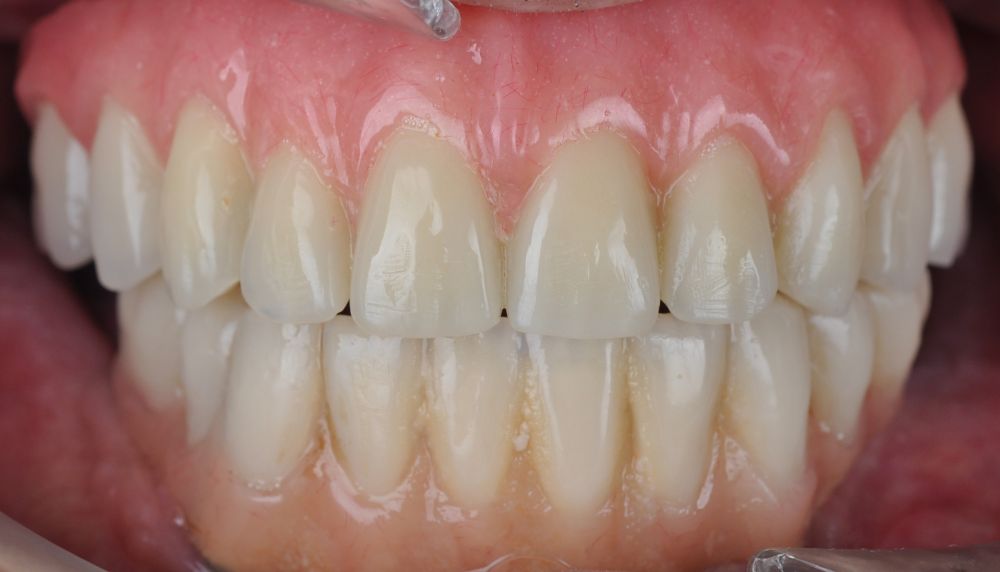

Clinical Case: A subperiosteal sintered titanium structure was fabricated with six transepithelial connections that were rehabilitated with an immediate implant supported fixed prosthesis made of PMMA. Two months later, a sintered chromium-cobalt framework with machined bases covered with acrylic resin teeth was fabricated as the final restoration. At one year follow-up, the case remains stable.